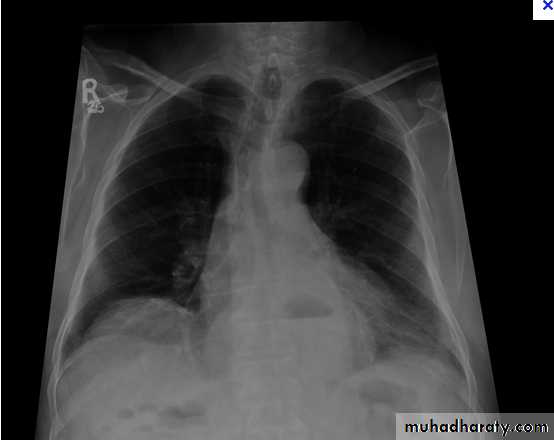

Massive pleural effusion with mediastinal shift to the left.

(A) Chest radiograph(B) CT coronal reconstruction. A massive effusion displaces the mediastinum to the left. CT shows the important pleural effusion together with the enhanced atelectatic left lung.

Note also the depression of the right hemidiaphragm (arrows).